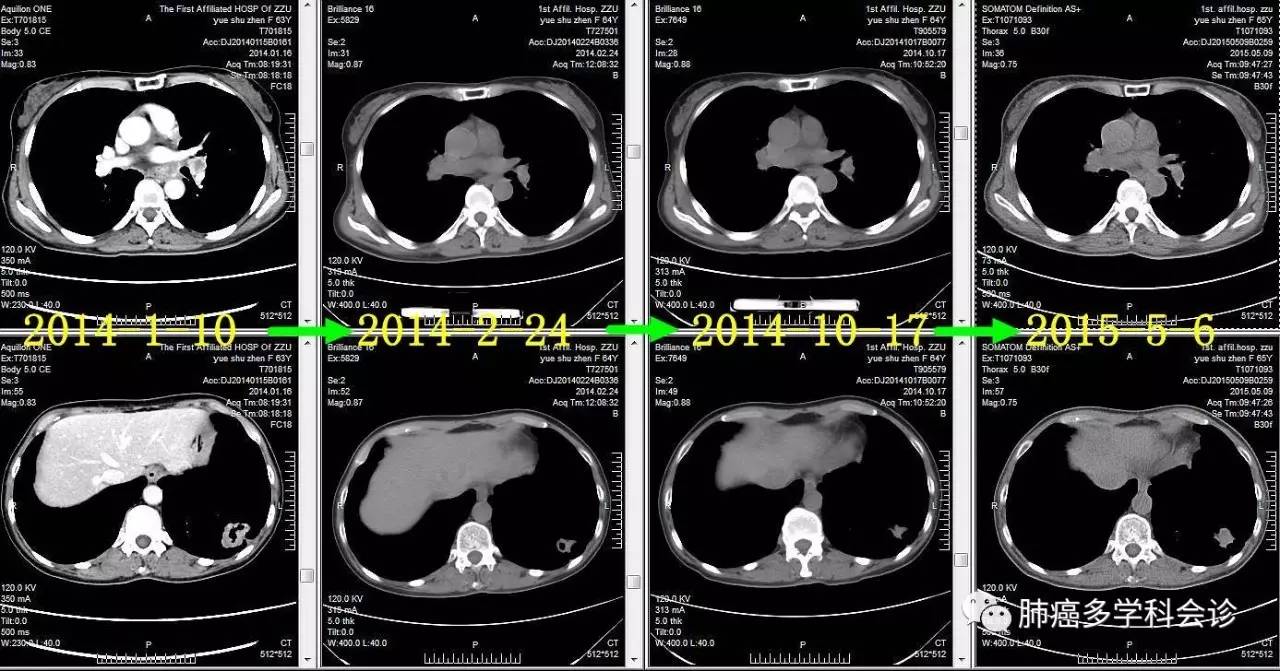

患者岳SZ,女,68岁。2014年1月,因咳嗽吐痰做CT发现左下肺占位、纵隔和双肺门淋巴结肿大;头颅MRI发现左侧额叶转移瘤。SPECT示:左侧第2前肋局部骨代谢异常活跃,结合CT考虑骨折。

●2014.01 ~ 2016.03 口服易瑞沙获部分缓解,服药共2年余后因疾病进展而停用。以下是治疗过程中胸部肿瘤CT图像的变化:

微信图片_20170523115459.jpg